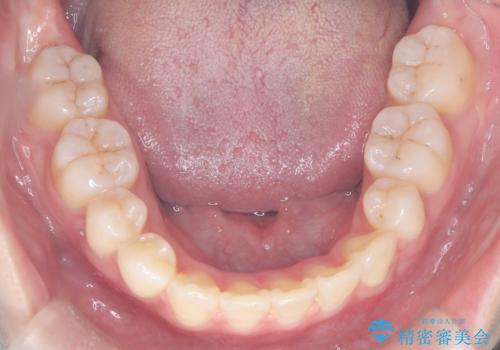

- 患者様は下顎の前歯が3本しかないという特異な歯列を持ち、噛み合わせのバランスが崩れていました。上下の歯の本数が通常と異なるため、抜歯部位の選定が重要となるケースでした。診査の結果、歯の位置や咬合のバランスを考慮し、上顎の両側小臼歯2本と左下の小臼歯1本を抜歯することで、上下の噛み合わせを整える方針としました。矯正装置は、**目立ちにくいハーフリンガル(上顎は裏側矯正・下顎は表側矯正)**を採用しました。

まず、計画通りに抜歯を行い、歯列のスペースを確保しました。上顎は裏側矯正(リンガル)で目立たないように配慮しながら歯を後方へ移動し、下顎は表側矯正を使用して、3本の前歯の位置関係を調整。上下の歯の噛み合わせを細かくコントロールしながら、全体のバランスを整えました。治療後は「歯並びがきれいになり、噛み合わせもしっかり合うようになった」と患者様にも満足していただけました。